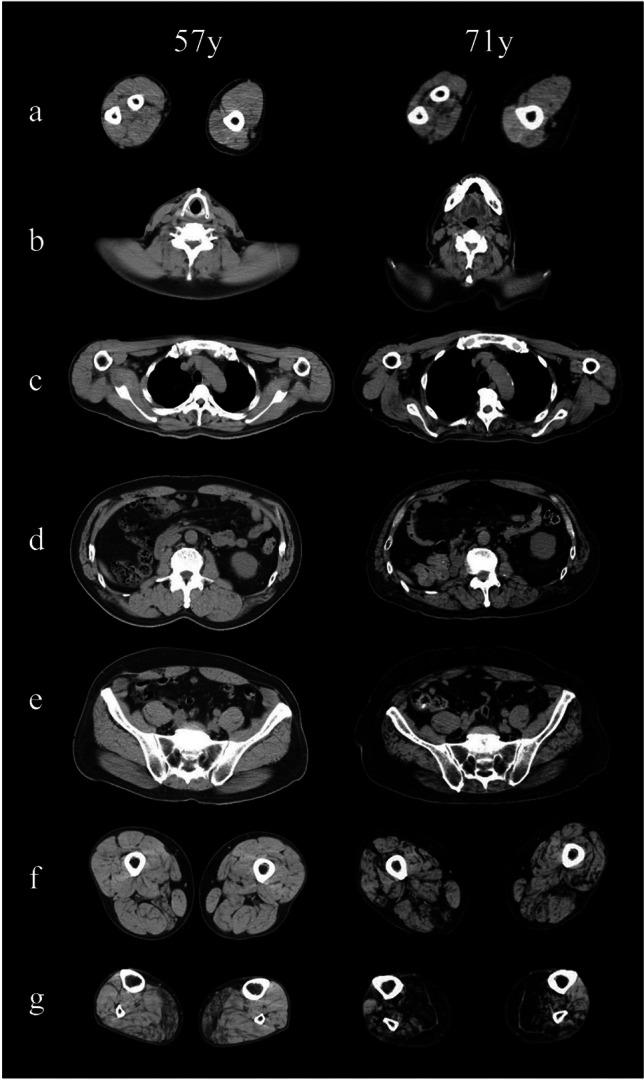

Cerebellar ataxia, neuropathy, and vestibular areflexia syndrome (CANVAS) is an autosomal recessive multisystem neurologic disorder caused by biallelic intronic repeats in RFC1. Although the phenotype of CANVAS has been expanding via diagnostic case accumulation, there are scant pedigree analyses to reveal disease penetrance, intergenerational fluctuations in repeat length, or clinical phenomena (including heterozygous carriers). We identified biallelic RFC1 ACAGG expansions of 1000 ~ repeats in three affected siblings having sensorimotor neuronopathy with spinocerebellar atrophy initially presenting with painful muscle cramps and paroxysmal dry cough. They exhibit almost homogeneous clinical and histopathological features, indicating motor neuronopathy. Over 10 years of follow-up, painful intractable muscle cramps ascended from legs to trunks and hands, followed by amyotrophy and subsequent leg pyramidal signs. The disease course combined with the electrophysical and imagery data suggest initial and prolonged hyperexcitability and the ensuing spinal motor neuron loss, which may progress from the lumbar to the rostral anterior horns and later expand to the corticospinal tract. Genetically, heterozygous ACAGG expansions of similar length were transmitted in unaffected family members of three successive generations, and some of them experienced muscle cramps. Leukocyte telomere length assays revealed comparatively shorter telomeres in affected individuals. This comprehensive pedigree analysis demonstrated a non-anticipating ACAGG transmission and high penetrance of manifestations with a biallelic state, especially motor neuronopathy in which muscle cramps serve as a prodromal and disease progress marker. CANVAS and RFC1 spectrum disorder should be considered when diagnosing lower dominant motor neuron disease, idiopathic muscle cramps, or neuromuscular hyperexcitability syndromes.

小脑共济失调、感觉运动神经病和前庭反射消失综合征(CANVAS)是一种常染色体隐性多系统神经疾病,由 RFC1 中的双等位基因内含子重复引起。尽管通过诊断病例积累扩展了 CANVAS 的表型,但很少有家族分析来揭示疾病的外显率、重复长度的代际波动或临床现象(包括杂合携带者)。我们在三个受影响的兄弟姐妹中发现了双等位基因 RFC1 ACAGG 扩展,长度为 1000 个重复,这些兄弟姐妹患有感觉运动神经元病伴脊髓小脑萎缩,最初表现为伴有肌肉痉挛和阵发性干咳的疼痛性肌肉痉挛。他们表现出几乎相同的临床和组织病理学特征,表明运动神经元病。在超过 10 年的随访中,从腿部到躯干和手部的疼痛性难治性肌肉痉挛逐渐加重,随后出现肌肉萎缩和随后的腿部锥体征。疾病过程结合电生理和影像学数据表明,最初和持续的过度兴奋以及随后的脊髓运动神经元丧失,可能从腰椎进展到头侧前角,随后扩展到皮质脊髓束。遗传上,三代未受影响的家族成员中存在类似长度的杂合 ACAGG 扩展,其中一些人经历了肌肉痉挛。白细胞端粒长度测定显示受影响个体的端粒相对较短。这项全面的家系分析表明,ACAGG 呈非预期传递且表现出高外显率,尤其是运动神经元病,其中肌肉痉挛是前驱期和疾病进展的标志物。在诊断下运动神经元病、特发性肌肉痉挛或神经肌肉过度兴奋综合征时,应考虑 CANVAS 和 RFC1 谱障碍。